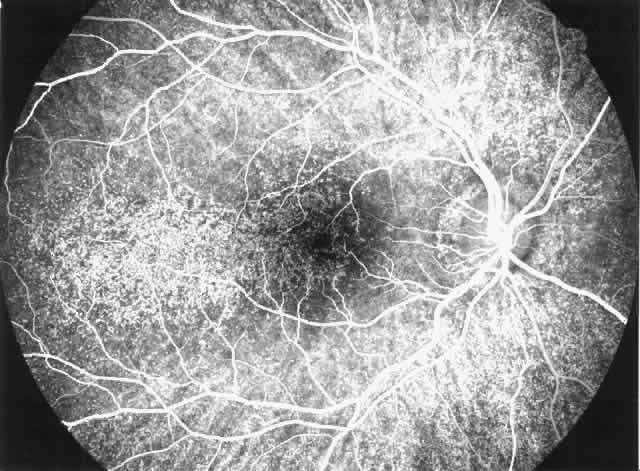

Fig. 1. Malignant hypertension with retinal and choroidal vascular manifestations: retinal hemorrhages, exudative retinal detachment, numerous edematous Elschnig's spots (A), and fluorescein angiographic abnormalities with areas of hypoperfusion of the choriocapillaris in the early phase (B), and diffuse leak of fluorescein in the late phase of angiography (C).

Drusen-like lesions and retinal pigment epithelium damage have also been recognized as a feature of MPGN type II.72–79 In a fluorescein angiographic study of 26 patients who had biopsy-proven MPGN type II, specific fundus lesions were identified in 24 patients (92%).79 Two adolescents with a history of renal disease of 13 months and 2 months had normal fundi. Small-sized lesions similar to small hard drusen were observed in all 24 patients with a history of renal disease lasting for 16 months or more (Fig. 6). In all 15 subjects with a history of renal disease of at least 12 years, larger drusen-like lesions were also noticed. In all 11 patients with renal disease persisting for 18 years or more, drusen occupied most of the fundus and areas of geographic atrophy were seen as well. Foci of new vessels and disciform scarring were observed in eight eyes of five patients with a renal history of 15 years or more (Fig. 7). Most eyes that did not show subretinal neovascularization had normal or nearly normal vision and visual fields. Three patients, however, exhibited ocular symptoms, which were related to pronounced macular atrophic changes, hypertensive retinopathy, and cataracts. The type of fundus lesions was statistically correlated (p<0.0001) with the duration of the renal disease, but not with age, sex, or renal insufficiency. Fundus changes between first and last visit as well as cross-sectional studies suggest a slow progression of retinal disease, which is probably independent of treatment and age of the patient.77–79

Fig. 6. Specific fundus lesions of membranoproliferative glomerulonephritis type II in a 12-year-old child with renal disease since the age of 3 years. The fluorescein angiogram shows numerous small lesions similar to hard drusen. (Leys A, Vanrenterghem Y, Van Damme B et al: Fundus changes in membranoproliferative glomerulonephritis type II: A fluorescein angiographic study of 23 patients. Graefes Arch Clin Exp Ophthalmol 229:406, 1991)